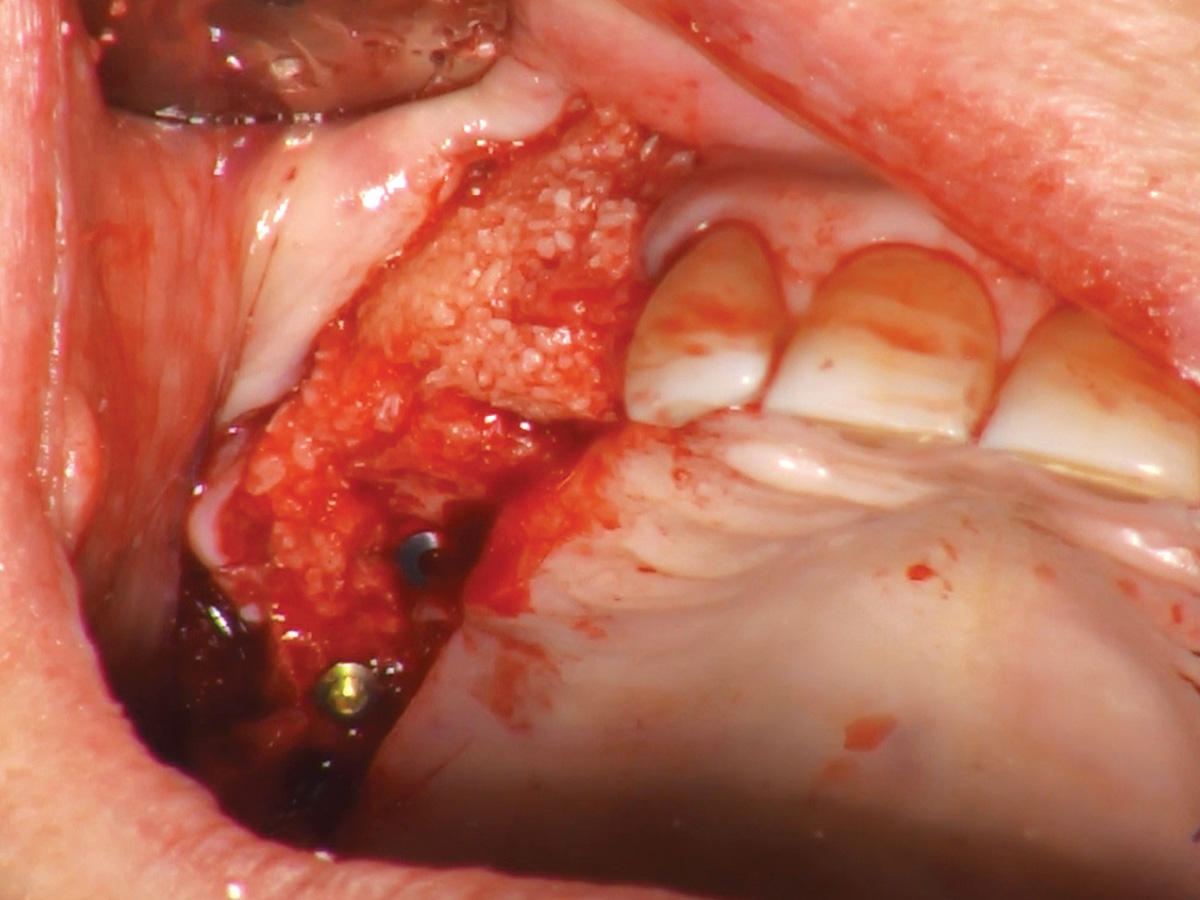

Abbildung 5

Das OsteoBiol® GTO® im Sinus und rund um die Implantate wird kompaktiert.

Abbildung 7

Einsetzen der Gingivaformer nach vier Monaten.

Abbildung 8

Wundverschluss, Okklusalansicht.